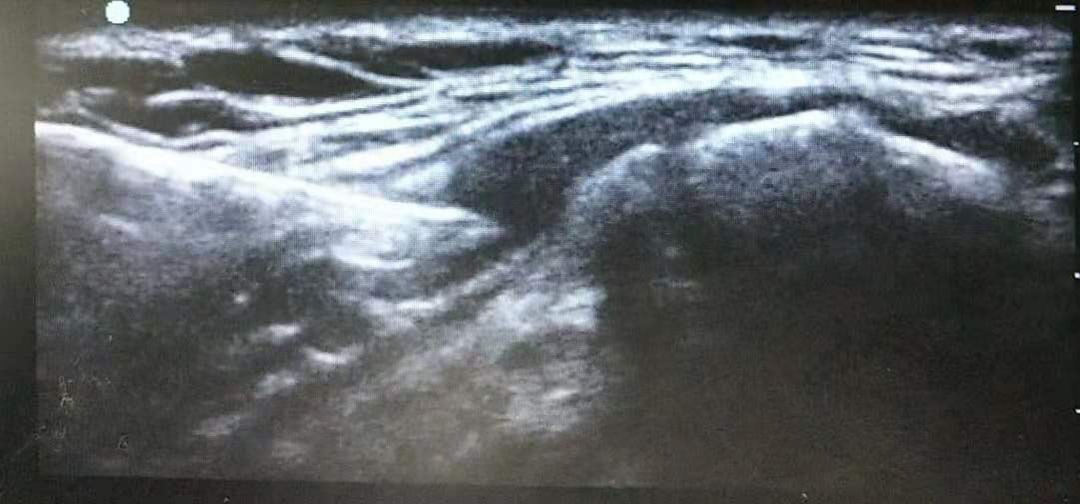

超聲引導(dǎo)技術(shù)就可以順利解決這些問題,超聲可以比較清晰地顯示目標(biāo)神經(jīng)和血管的結(jié)構(gòu),在超聲引導(dǎo)下,穿刺針的行進(jìn)路線也可實(shí)時(shí)觀測(cè),實(shí)現(xiàn)了操作的可觀化;以及發(fā)現(xiàn)異常的神經(jīng)與血管間的結(jié)構(gòu)的變異,還可以觀察注藥過程中藥液的擴(kuò)散情況,避免誤入血管及損傷重要的臟器與組織,從而提高了神經(jīng)阻滯麻醉的成功率并減少了并發(fā)癥。超聲引導(dǎo)技術(shù)幾乎可以用于任何患者,甚至在全麻肌松狀態(tài)下也可實(shí)施。